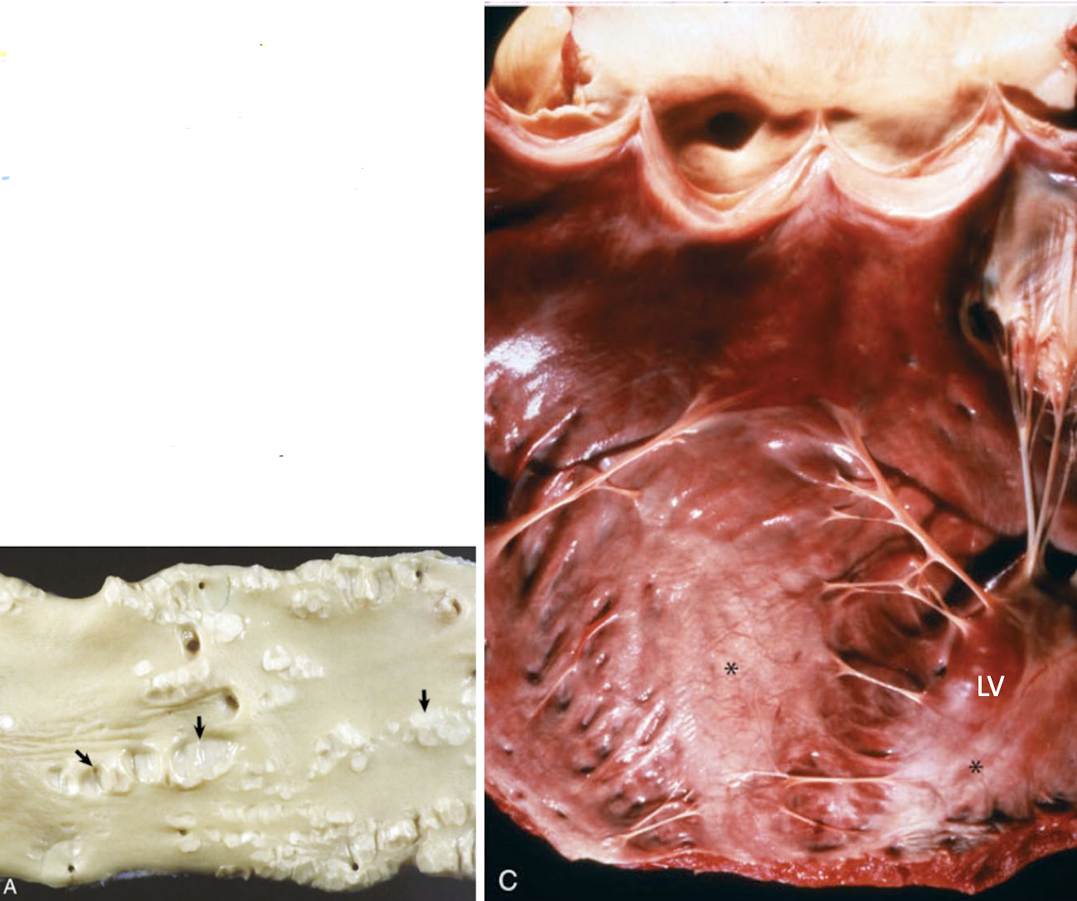

What is this showing?

hematocysts and lymphocysts

endocardial mineralization

endocardial mineralization due to vitamin D toxicosis